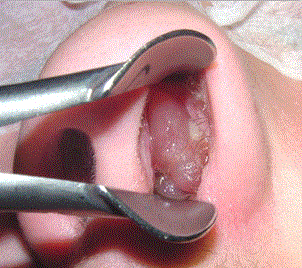

Si le traitement médicamenteux ne diminue pas ou ne supprime pas les polypes nasosinusiens, il se peut que vous ayez besoin d’une chirurgie endoscopique pour éliminer les polypes et pour corriger les problèmes de sinus qui les rendent propices à l’inflammation et au développement des polypes.

Pendant la chirurgie endoscopique, le chirurgien insère un petit tube avec une petite caméra (endoscope) dans vos narines et le guide dans vos cavités sinusiennes. Il ou elle utilise des instruments miniaturisés spécifiques pour enlever les polypes (polypectomie) et les obstacles qui bloquent l’écoulement des fluides de vos sinus notamment au niveau du sinus maxillaire (méatotomie).

Votre chirurgien peut également ouvrir l’ensemble des sinus paranasaux pour permettre l’ablation d’une grande partie des cloisons nasales favorisant la récidive des polypes (ethmoïdectomie totale). La chirurgie endoscopique est effectuée sous anesthésie générale, lors d’une hospitalisation avec une nuit à l’hôpital ou en ambulatoire.